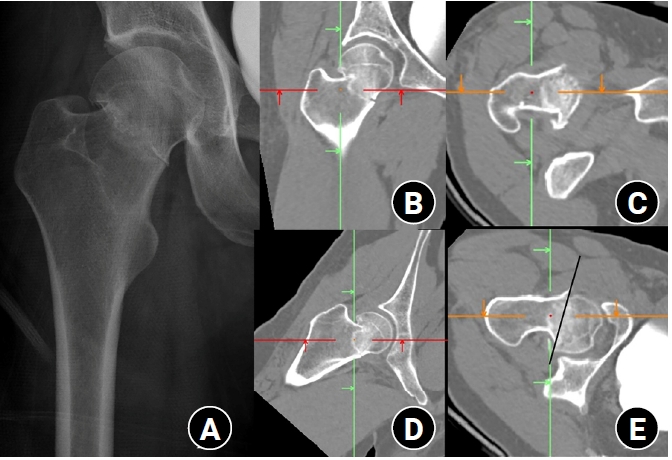

Data sources and measurement

Fig. 1.

After the proximal femur was selected as a cropping area, the scanning plane was reformatted parallel to the neck midline of the neck-shaft fragment in the axial plane. The proximal femur was then realigned vertically to the ground in the coronal plane using tools of Mimics software. Then, fracture morphologies were assessed in coronal (A), axial (B), sagittal (C), and three-dimensional biplanar plane (D).

Fig. 1. After the proximal femur was selected as a cropping area, the scanning plane was reformatted parallel to the neck midline of the neck-shaft fragment in the axial plane. The proximal femur was then realigned vertically to the ground in the coronal plane using tools of Mimics software. Then, fracture morphologies were assessed in coronal (A), axial (B), sagittal (C), and three-dimensional biplanar plane (D).